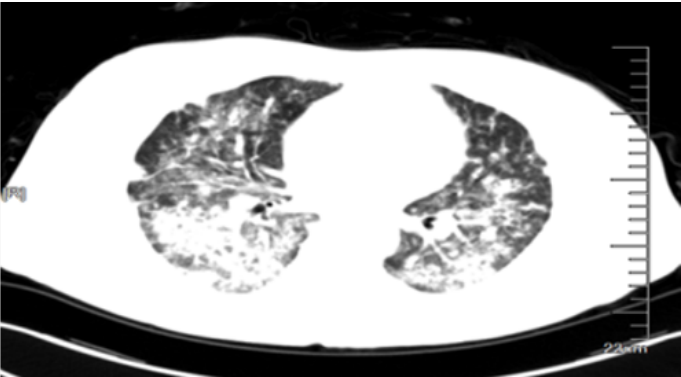

患者,女,50岁;活动后喘息20天,加重伴发热3天,2021年11月19日转入我院。入院胸部CT显示:双肺实变,磨玻璃影(图1)。11月24日复查胸部CT可见病变进展迅速(图2)。予患者气管插管机械通气、俯卧位等,呼吸衰竭未见改善。遂于11月25日启动VV-ECMO(转速2860 rpm,流量4.5 L/min,氧浓度100%)。追问病史:患者入院前1月有活动后气促症状,自觉全身不适,近2年有眼干、口干不适。进一步检查发现,ANA反应阳性(+),ANA核型为胞浆颗粒型(异常);抗SSA/Ro抗体阳性(++)、抗Ro-52抗体阳性(+++)。诊断:急性间质性肺炎(AIP);Ⅰ型呼吸衰竭;混合性结缔组织病。治疗:VV-ECMO+呼吸机辅助通气+俯卧位通气、激素(甲强龙80 mg×7天,60 mg×3天,40 mg qd)、免疫抑制剂(环磷酰胺400 mg qd×3天)、抗感染(哌拉西林他唑巴坦4.5 g q12h+莫西沙星0.4 g qd+氟康唑氯化钠注射液20 mg qd)、抗凝等。在随后的一段时间内,患者影像学改善不明显(图3)。直至12月20日,复查胸部CT可见患者肺部病变较前明显吸收(图4)。2021年12月31日VV-ECMO撤机后,继续气切呼吸机辅助通气,甲强龙40 mg qd抗炎治疗,继续抗感染治疗,2022年1月7日脱机,1月21日气管封管,1月26日出院。后续治疗:强的松25 mg qd,环磷酰胺600 mg q2w×4次,序贯吗替麦考酚酯0.5 g bid。重症间质性肺疾病(ILD)在诊断方面需要考虑以下问题:是ILD吗?是哪种ILD?严重程度如何?在治疗方面,除了生命支持(呼吸支持重点)和病因治疗,并发症的处理也至关重要。重症ILD的诊断包括两方面,一方面是通过影像学、病史+临床表现、BALF-NGS、实验室检查、肺活检等对ILD进行诊断;另一方面涉及重症,患者多面临呼吸衰竭甚至多器官衰竭,因此时间更加紧迫。在ICU内最常见的重症ILD包括:特发性肺纤维化急性加重(AE-IPF)、自身免疫相关性ILD、肿瘤治疗相关性ILD、隐源性机化性肺炎(COP)、AIP、过敏性肺炎(HP)、急性嗜酸性粒细胞性肺炎(AEP)、药物相关ILD等。在影像学方面,最易导致重症的类型有弥漫性磨玻璃影和实变影。最常见的鉴别诊断就是重症肺部感染。表现为弥漫性磨玻璃影或实变影的ILD较为多见,例如:HP、嗜酸性粒细胞性肺炎(EP)、结缔组织病相关间质性肺病(CTD-ILD)、非特异性间质性肺炎(NSIP)、脱屑性间质性肺炎(DIP)、淋巴细胞性间质性肺炎(LIP)、机化性肺炎(OP)、AE-IPF、肺泡蛋白沉积症(PAP)、肺泡微结石症、结节病、弥漫性肺泡出血综合征、肺水肿等。而很多感染性疾病影像学也可表现为磨玻璃影,例如:卡氏肺孢子菌肺炎(PCP)、病毒性肺炎、巨细胞病毒性肺炎、支原体肺炎。尽管如此,ILD也有部分影像学具有特征性,可以被识别。图5左表现为肺陷闭,也称为“猪头肉冻征”,这是典型的亚急性HP的影像学特征。图5右表现为弥漫性磨玻璃影,但以肺门向外扩展,外面有肺大泡,这是典型的PCP表现。临床上多见自身免疫性疾病导致的ILD,此类疾病也具有共同的特征,例如双肺弥漫,病理方面以NSIP或OP为主要特征。但也有部分患者可以出现弥漫性肺泡损伤(DAD)特征。如图6所示,左图为ANCA相关性血管炎,右图为MDA5相关性间质性肺病。因此,一定要警惕容易发生这种病理改变的自身免疫性疾病。